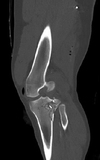

A 60-year-old man sustains a Gustilo type IIIB open fracture of the distal left tibia during a boating accident. There is severe contamination of the wound, and the patient undergoes multiple formal washouts in the operating room. There is no neurovascular compromise of the extremity. He undergoes external fixation to stabilize the limb. Which of the following is the most appropriate next step in treatment?

The correct response is Option A.

The Gustilo classification describes open fractures of the tibia by the severity of the soft tissue injury overlying the fracture. In patients with IIIB injuries, there is extensive soft-tissue loss and periosteal stripping, but no vascular compromise requiring repair.

Gustilo classification:

Type I: The wound is less than 1 cm long. There is little soft-tissue damage and no sign of crush injury. There is no or minimal comminution of the fracture.

Type II: The laceration is more than 1 cm long but there is no extensive soft tissue damage, flap, or avulsion. There is slight to moderate crushing injury, moderate comminution of the fracture.

Type III: Extensive damage to the soft tissues, including muscle, skin, and neurovascular structures, and a high degree of contamination.

Type IIIA: Soft tissue coverage of the bone is adequate.

Type IIIB: Extensive injury to or loss of soft tissue, with periosteal stripping and exposure of bone, massive contamination, and severe comminution of the fracture from high-velocity trauma

Type IIIC: Any open fracture with a vascular injury requiring repair.

Free tissue transfer will bring healthy, nontraumatized tissue into the area to cover the exposed broken bone. Multiple recent studies have shown equivalence of muscle versus skin/fat/fascia flaps for coverage of the open fracture even in patients with osteomyelitis. Negative pressure wound therapy has proven to be an excellent adjunct in the management of patients with these injuries. Between washouts, negative pressure devices can help decrease edema and isolate the wound and bone from the outside world. In a patient with a IIIB injury, there is insufficient tissue available to cover the wound. Therefore, secondary intention would not close the wound.

Split-thickness skin grafting provides an epithelial barrier to help seal off a wound from outside contamination. Grafts require a viable wound bed to survive. There must be a pliable bed to help grafts resist minor trauma in the future. With the periosteal stripping in this type of injury, a graft would not survive. In addition, graft placed directly on bone with periosteum would be very vulnerable to breakdown from minor trauma.

Bone allografting can be used to bridge defects in many circumstances. In the patient described, the severe contamination of the initial injury would make bone allografting much less appealing than autografting. Because of contamination, any type of bone grafting may need to be delayed until after achieving stable soft tissue coverage of the fracture.

A pedicled gastrocnemius muscle flap provides excellent coverage for defects about the knee, including the proximal tibia. Although the free gastrocnemius muscle flap could be transferred to any location, the pedicled flap would not be able to reach the distal tibia.